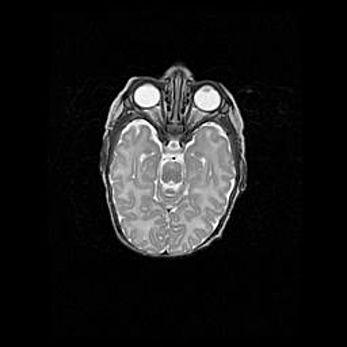

Мальформация Денди-Уокера. Киста задней черепной ямки.

Агенезия мозолистого тела.

Возраст: 2,5 месяца

Вес: 2420 г

Пол: женский

Окружность головы: 37 см

Срок гестации: 32 недели

Мальформация Денди—Уокера — редкий вид патологии ЦНС, представляющий собой врожденный порок развития каудального отдела ствола и червя мозжечка, ведущий к неполному раскрытию срединной (Мажанди) и латеральных (Лушка) апертур IV желудочка мозга. Для этогно синдрома характерна триада симптомов: гипотрофия червя мозжечка и/или полушарий мозжечка, кисты задней черепной ямки, гидроцефалия различной степени. В 70% случаев порок сочетается и с другими аномалиями головного мозга, в частности с агенезией мозолистого тела.